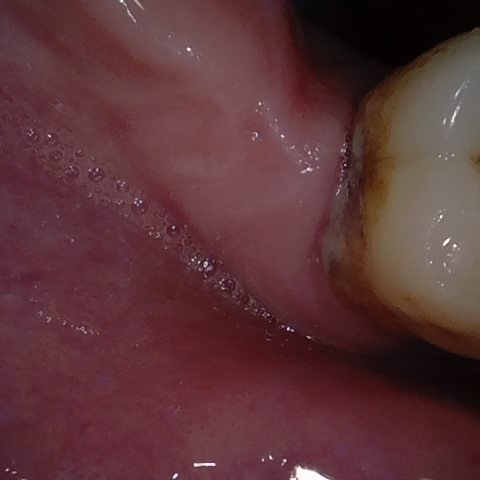

Annotated as "Good"